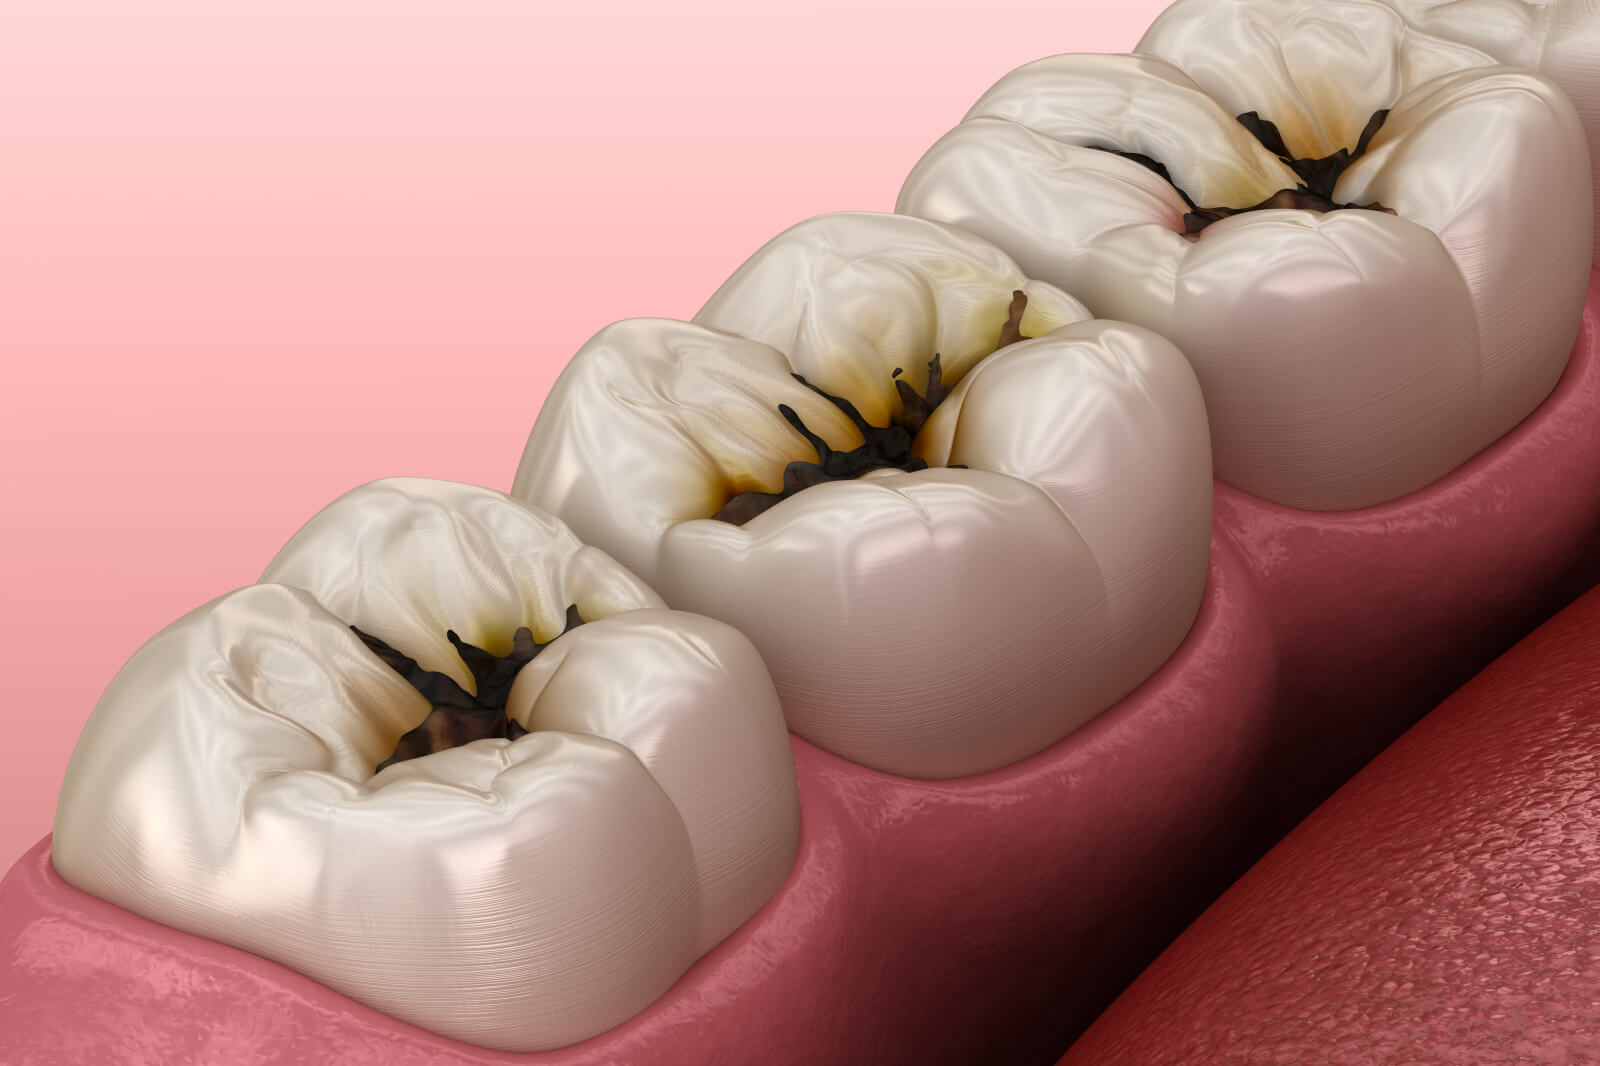

충치 치료

One Day 인레이 – 하루 만에 끝내는 충치 치료

충치 치료, 더 이상 미루거나 두려워하지 마세요.

직장‧학교‧가사로 바쁜 요즘, 2-3회 내원은 큰 부담이 됩니다.

플란트구강악안면외과 치과는 3D 디지털 스캔+설계+밀링 시스템으로 인레이 제작-부착을 당일에 완료해 시간을 확 줄였습니다.